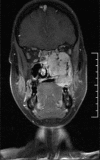

Inflammatory myofibroblastic tumor (IMT) is a rare tumor of uncertain origin with variable biological behavior ranging from reactive lesions to highly aggressive malignancy. Oral IMTs are extremely rare and only 25 cases had been reported so far. A case of IMT with sarcomatous transformation in an extraction site with a history of tooth extraction following tooth mobility of an upper left molar tooth is presented here. The tooth was extracted following a complaint of gingival swelling and mobility of tooth. Though malignant transformation in IMTs had been documented in the extra oral sites, wide search of associated literature suggests, this is the first case of oral IMT showing malignant change associated with gingiva. The case report attempts to highlight the variant possibilities of tooth mobility other than periodontitis and the importance of assessing the primary cause of such conditions.